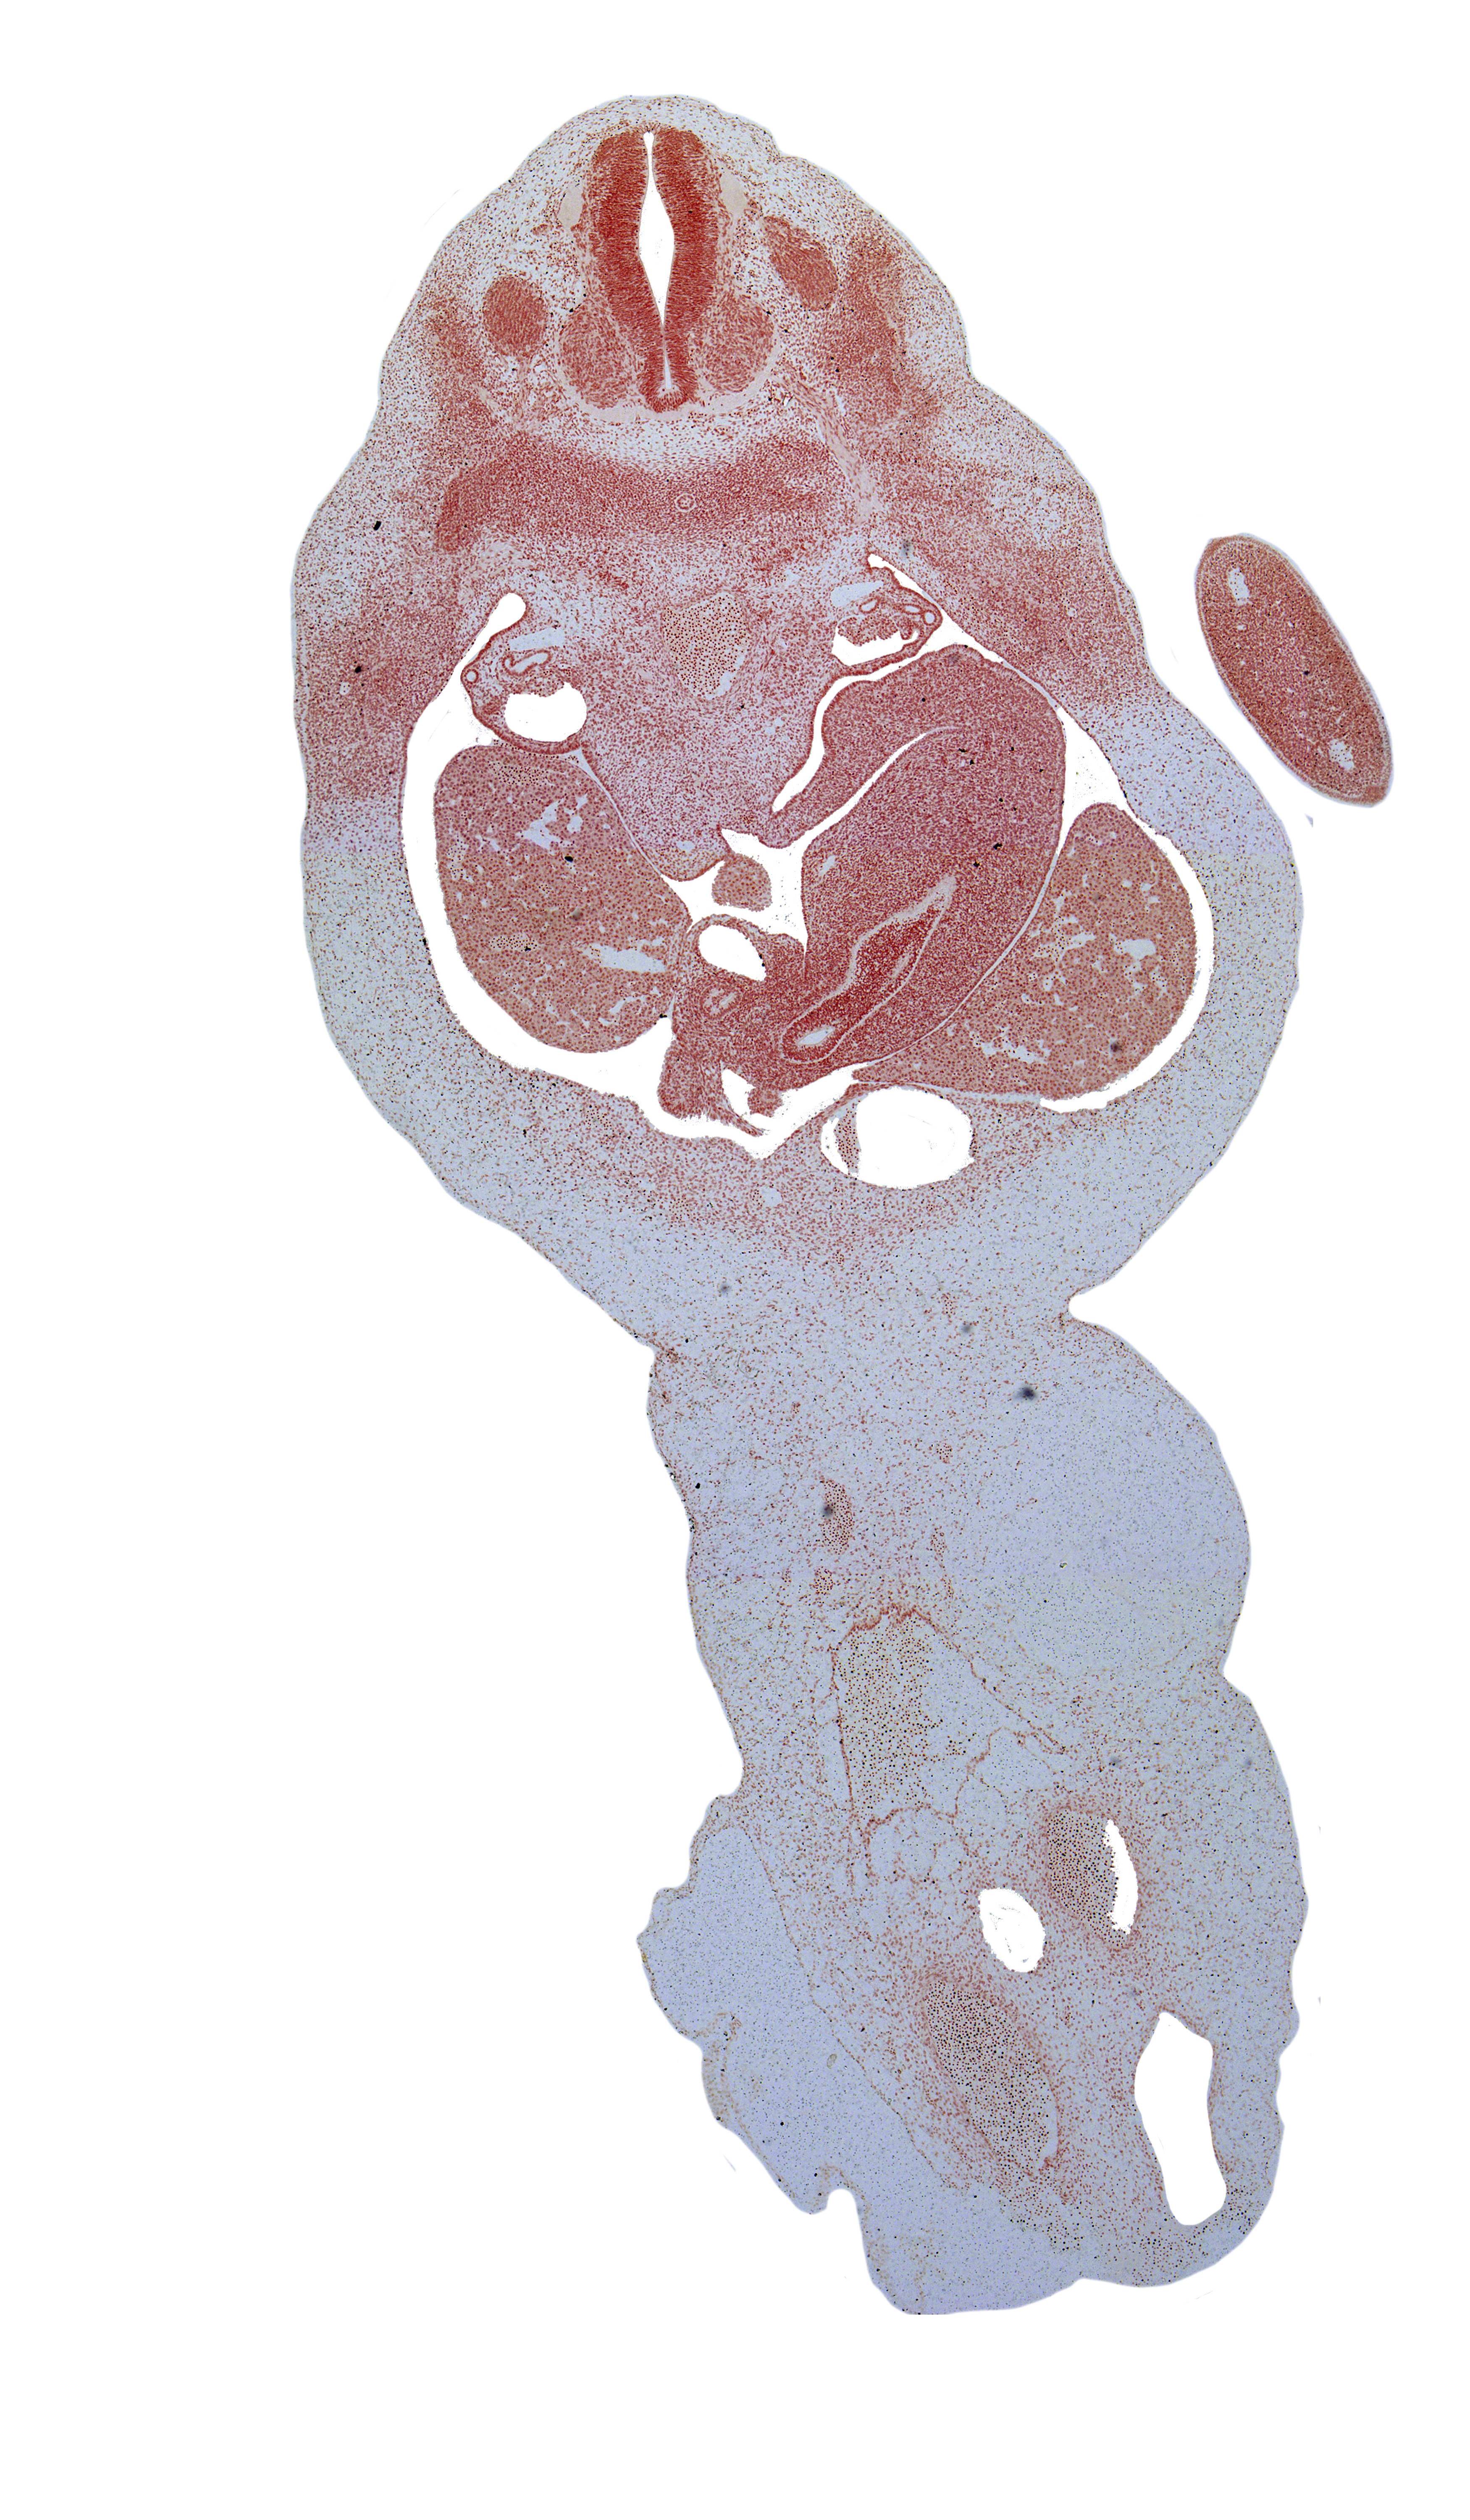

Carnegie Embryo #6517 | Location: 30-01-01

Keywords: T-2 spinal ganglion, T-3 dorsal primary ramus, T-3 ventral primary ramus, allantois, aorta, caudal edge of stomach, duodenum, epiploic foramen, greater sac, hepatic portal vein, junction of common hepatic and cystic ducts, left lobe of liver, left umbilical artery, lesser sac (omental bursa), right lobe of liver, right umbilical artery, spleen, umbilical vein

Source: The Virtual Human Embryo.